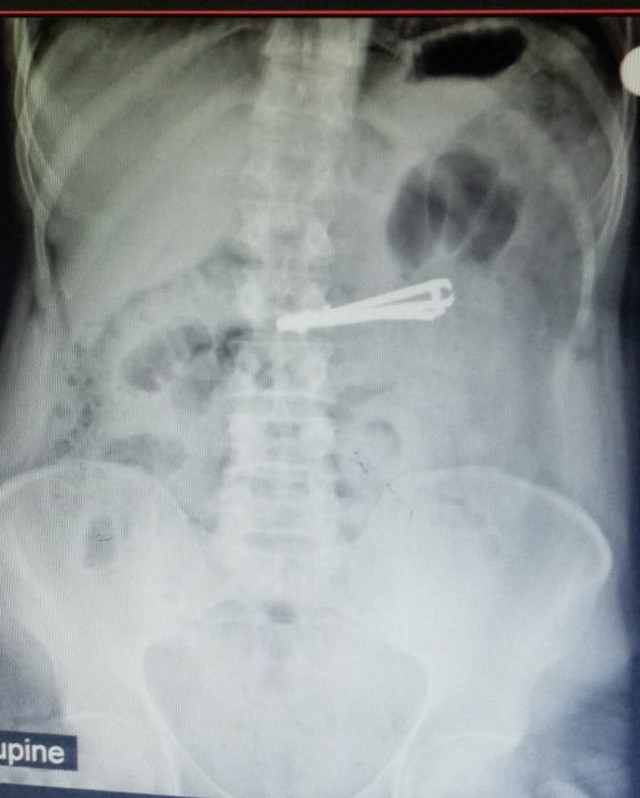

SİİRT'te 42 yaşındaki bir kişinin yuttuğu tırnak makası midesinden endoskopi uygulamasıyla çıkarıldı.

Abone olSiirt'in Kurtalan ilçesinde yaşayan ve doğuştan ağır mental retardasyon (zeka geriliği) hastası Mutih Akurt (42), elindeki tırnak makasını ağzına atarak yuttu. Akurt, yakınlarının durumu fark etmesi üzerine kaldırıldığı Kurtalan Devlet Hastanesinde yapılan tetkiklerin ardından Siirt Eğitim ve Araştırma Hastanesine sevk edildi.

Hastanın midesindeki tırnak makası, Genel Cerrahi Uzmanı Dr. Yasemin Küçük'ün yaptığı endoskopiyle çıkarıldı. Korkulan olmadan sağlığına kavuşan Akurt, daha sonra taburcu edildi.